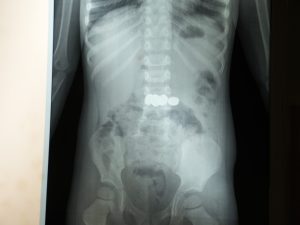

മേപ്പാടി: രണ്ട് വയസ്സുകാരൻ വിഴുങ്ങിയ അഞ്ച് ബാറ്ററികൾ സമയബന്ധിതമായ എൻഡോസ്കോപ്പി നടപടിയിലൂടെ വിജയകരമായി പുറത്തെടുത്ത് ഡോ. മൂപ്പൻസ് മെഡിക്കൽ കോളേജ് ഗാസ്ട്രോ എന്ററോളജി വിഭാഗം കുട്ടിയുടെ ജീവൻ രക്ഷിച്ചു.

ഗാസ്ട്രോ എന്ററോളജി വിഭാഗം സ്പെഷ്യലിസ്റ്റ് ഡോ. സൂര്യനാരായണ നടത്തിയ എൻഡോസ്കോപ്പി നടപടിയിലൂടെയാണ് ബാറ്ററികൾ സുരക്ഷിതമായി പുറത്തെടുത്തത്. വയറ്റിലെ ശക്തമായ അസിഡിക് പ്രവർത്തനത്തിന്റെ ഫലമായി ബാറ്ററികൾ പൊട്ടിപ്പോകാനുള്ള സാധ്യത വളരെ കൂടുതലാണെന്നും, അങ്ങനെ സംഭവിച്ചാൽ ബാറ്ററിയിൽ നിന്നു പുറന്തള്ളപ്പെടുന്ന രാസവസ്തുക്കൾ കുടൽ, കരൾ തുടങ്ങിയ പ്രധാന അവയവങ്ങൾക്ക് ഗുരുതരമായ ക്ഷതം ഉണ്ടാക്കുമെന്നും ഡോക്ടർ വ്യക്തമാക്കി. അത്തരമൊരു സാഹചര്യത്തിൽ എൻഡോസ്കോപ്പിയിലൂടെ ബാറ്ററികൾ പുറത്തെടുക്കാൻ സാധിക്കാതെ പോയാൽ അത് കുട്ടിയുടെ ജീവന് തന്നെ ഭീഷണിയായേക്കുമായിരുന്നു എന്നും അദ്ദേഹം പറഞ്ഞു.സമയബന്ധിതമായ ചികിത്സ ലഭിച്ചതിനാലാണ് വലിയ അപകടം ഒഴിവാക്കാൻ സാധിച്ചതെന്നും, നിലവിൽ കുട്ടിയുടെ ആരോഗ്യനില തൃപ്തികരമാണെന്നും അധികൃതർ അറിയിച്ചു.